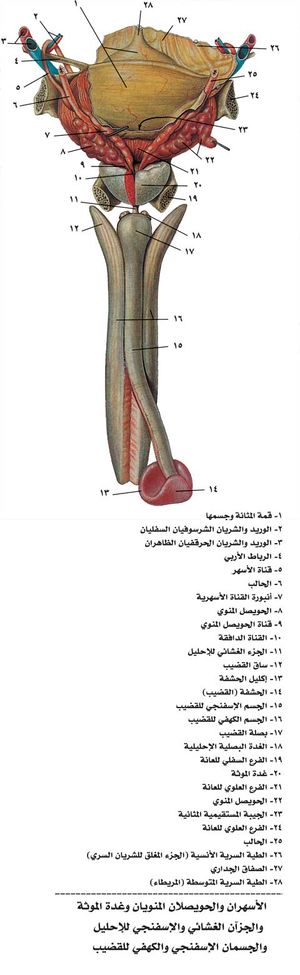

القضيب

وهو عضو الجماع والتبويل يتألف من الجسمين الكهفيين corporea cavernosa المشكلين من أسطوانتين إسفنجيتين في الظهر والجانبين ومن الجسم الإسفنجي spongiosum corpus في بطن القضيب، يمر فيه الإحليل الذي ينقل البول والسائل المنوي، ويبدأ بتوسع بصلي الشكل في العجان، وينتهي في ذروة القضيب بكتلة مخروطية الشكل تسمى الحشفة glans التي تغطيها القلفة prepuce.

فيزيولوجية القضيب

للقضيب وظيفتان الأولى: نقل البول والمني للوسط الخارجي بوساطة الإحليل، والثانية: هي الوظيفة الجنسية المتمثلة بالانتصاب أو النعوظ. وإن آلية الانتصاب معقدة نوعاً ما، ويدخل فيها عناصر عدة، ويمكن تبسيطها بما يأتي:

تتم عملية الانتصاب بتمدد شديد للجسمين الكهفيين وتوترهما من جراء احتقان الدم فيهما بحيث يكون مقدار الوارد الدموي للجسمين عالياً خاصة في مرحلة بدء الانتصاب. وكلما ازداد امتلاء الجسمين الكهفيين وتوترت المحفظة الليفية المحيطة بهما خمصت الأوردة التي تحمل الدم الصادر من الجسمين الكهفيين، وتعيق خروجه مدة قصيرة هي مدة دوام الانتصاب. ومما يحافظ على دوام الانتصاب أثناء الجماع تقلص العضلات الوركية الكهفية والوركية الإسفنجية بآلية عصبية انعكاسية نتيجة تنبه القضيب الآلي في أثناء الجماع.

أما بعد القذف فيحدث تنبيه ودي يؤدي إلى تقلص الشرايين الواردة للقضيب من جهة، كما أن المواد المفرزة من النهايات العصبية والمؤدية لاسترخاء عضلات كُهيفات الجسم الكهفي تستنفذ، وكلتا الآليتين تؤدي لتقلص هذه العضلات مفرغة الدم من الكُهيفات ومنقصة التوتر ضمن الجسم الكهفي مما يؤدي إلى انفتاح طرق العود الوريدي للجسم الكهفي التي كانت مضغوطة في مرحلة الانتصاب، ومن ثم عودة الدم إلى الأوردة القضيبية الراجعة وزوال الانتصاب.

آفات القضيب

يتألف القضيب من الجسمين الكهفيين وقناة الإحليل المحاطة بالجسم الإسفنجي الذي يتضخم في مقدمة القضيب ليشكل الحشفة ومن غلف صفاقية وضامة وجلدية. يمتد الغلاف الجلدي في مقدمة القضيب ليشكل القلفة التي تحيط بالحشفة.